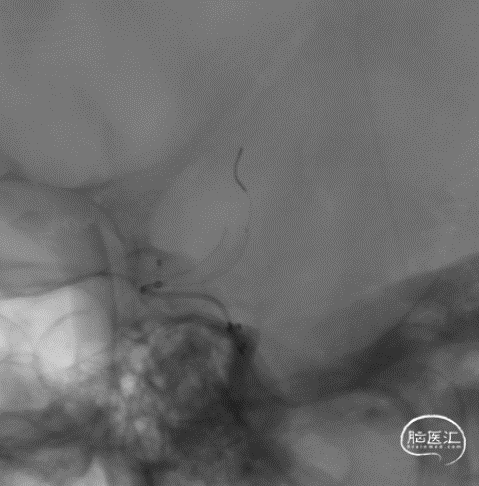

J-Tube™打开过程-整体显影性能良好。

J-Tube™血流导向密网支架打开过程。

动脉瘤近端血管狭窄

回收密网支架重新释放,狭窄依然存在。

释放J-Tube™血流导向密网支架。

释放支架后造影,可见血液滞留明显。

J-Tube™血流导向密网支架释放后处理狭窄。

Gateway 3.5*15 球囊到位

充盈球囊

球囊后处理效果。

处理前

处理后